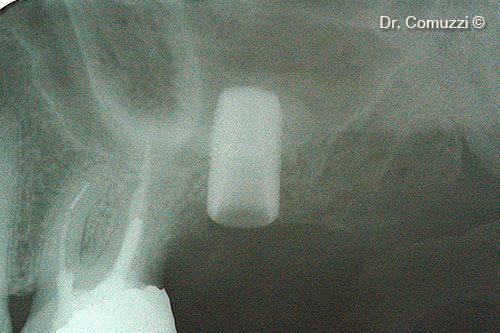

2. Initial vertical bone

6. X-ray of Sinus Lift at implant placement